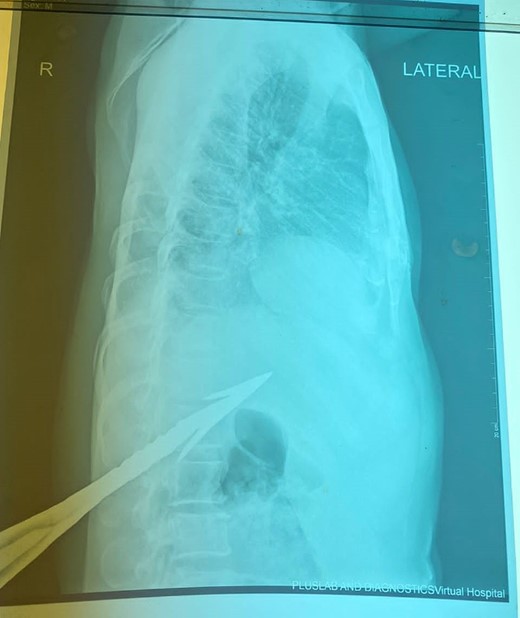

HB 9.9 mg/ml, sodium 135 mmol/L, chlorine 103 mmol/L, potassium 3.8 mmol/L, urea 4.3 mmol/L, and creatinine 108.5 umol/L. During the erect chest X-ray, the medical team observed the head of the spear within the abdominal cavity (Fig. 2), and a lateral chest X-ray confirmed its position in an ascending orientation (Fig. 3). The abdominal ultrasound showed the presence of a foreign body with an acoustic shade inside the liver parenchyma (Fig. 4); no free fluid was found in the Morrison’s pouch, but about 90 ml of free fluid was shown in the Douglass pouch. Both pleural spaces were free of fluid and had no pericardial fluid. We evaluated and discussed the possibility of performing an abdominopelvic computed tomography, but it was not feasible due to the patient's financial constraints.

Erect PA chest X-ray (impaled spear in the right hypochondrium).